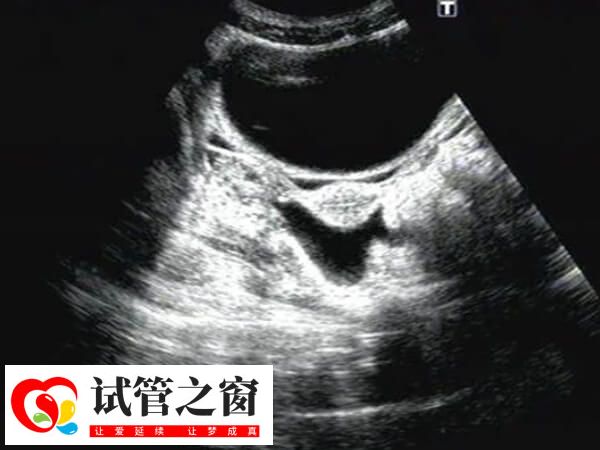

盆腔積液是女性生殖系統的常見癥狀表現,它不是一種疾病,確切地說是影像學對盆腔內液體的一種描述。正常情況下,患者做試管取卵后出現盆腔積液,那么可能會引起以下身體不適: